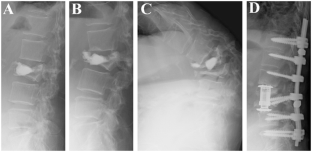

Severe kyphotic deformity resulting from collapses of cemented and adjacent vertebrae following percutaneous vertebroplasty using calcium phosphate cement. A case report

Percutaneous vertebroplasty (PVP) has been increasingly performed for the treatment of osteoporotic vertebral compression fracture. Despite its minimally invasive procedure, several complications associated with PVP have been reported, including adjacent-level vertebral fracture. Although rare, recollapse of the same vertebrae after PVP has also been reported. However, previous studies have not described a case in which collapses of both the cemented vertebrae and adjacent-level vertebrae occurred following PVP. Here, we report a rare case of severe kyphotic deformity resulting from collapses at the cemented and adjacent vertebrae after PVP using calcium phosphate cement (CPC). The patient required a highly invasive reconstruction procedure as a salvage surgery.

Fig. 1

Fig. 2